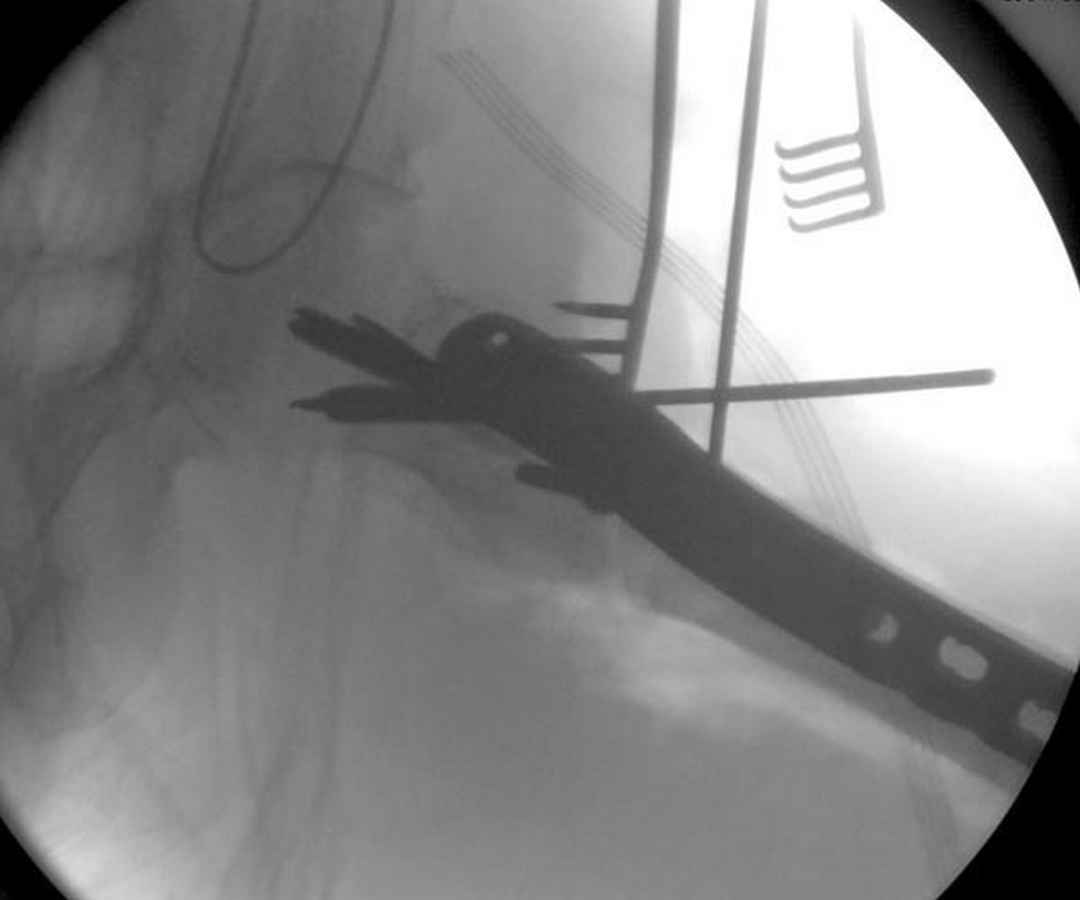

>Но современные пластины с угловой стабильностью не отстают от медуллярных конструкций. Межфрагментарные шурупы и имплант как нейтрализирующее создаст адекватную фиксацию.

судя по картинкам с ЭОПа явно использовались приемы непрямой репозиции под его контролем, а так же интраоперационный ЭОП-контроль положения винтов, без такого контроля операция может ухудшить ситуацию (опять же учтите сроки) т.к. результат буде зависеть в большей степени от искусства хирурга, а не от технологии